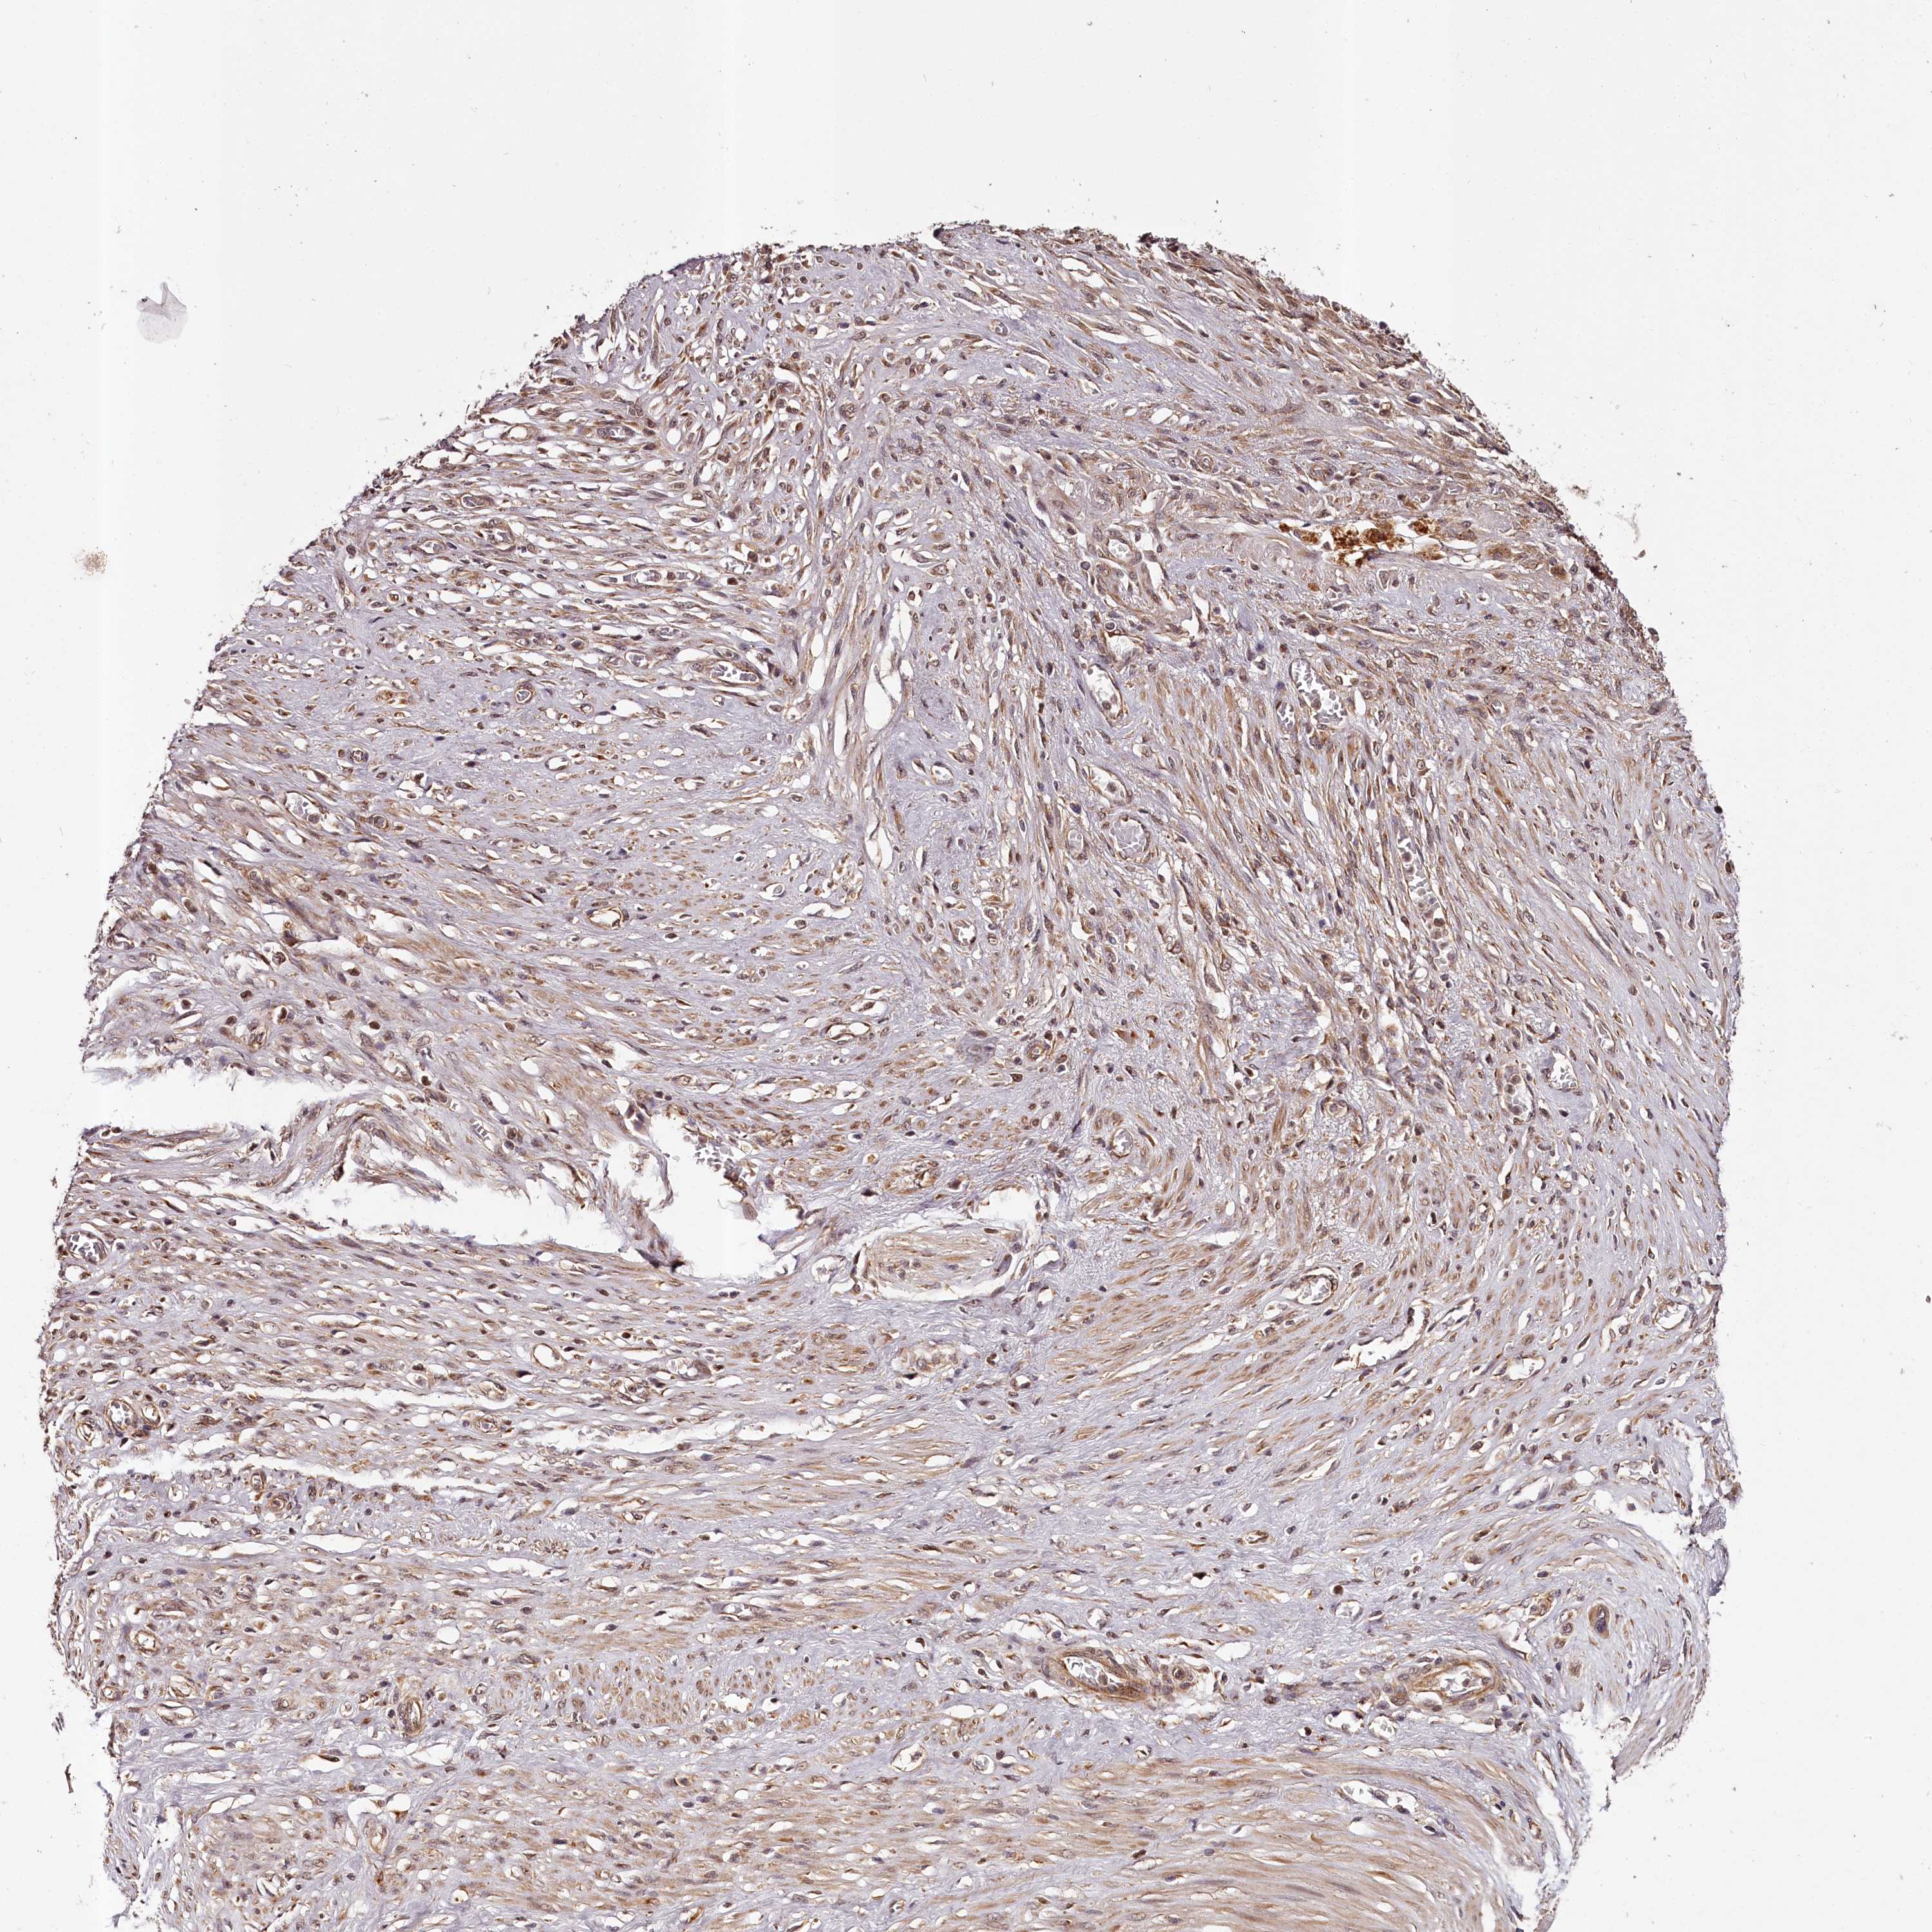

STOMACH CANCER - Protein expressioni

A mouse-over function shows sample information and annotation data. Click on an image to view it in a full screen mode. Samples can be filtered based on level of antibody staining by selecting one or several of the following categories: high, medium, low and not detected. The assay and annotation is described here.

Note that samples used for immunohistochemistry by the Human Protein Atlas do not correspond to samples in the TCGA dataset.

Antibody stainingi

Antibody staining in the annotated cell types in the current human tissue is reported as not detected, low, medium, or high, based on conventional immunohistochemistry profiling in selected tissues. This score is based on the combination of the staining intensity and fraction of stained cells.

Each image is clickable and will lead to virtual microscopy that enables deeper exploration of all samples and also displays staining intensity scores, fraction scores and subcellular localization as well as patient and tissue information for each sample.

Antibody HPA037717

Staining

High

Medium

Low

Not detected

Intensity

Strong

Moderate

Weak

Negative

Quantity

>75%

75%-25%

<25%

None

Location

Nuclear

Cytoplasmic/membranous

Cytoplasmic/membranous,nuclear

Adenocarcinoma, NOS

Adenocarcinoma, High grade